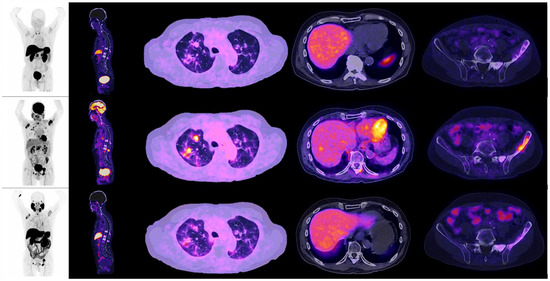

Figure 4. Patient number 7, a 67-year-old male, with an initial histopathological report of prostate adenocarcinoma, Gleason score 8 (4 + 4). Treated with androgen deprivation therapy + chemotherapy. Site of second biopsy was in a liver lesion, with a confirmatory histopathological report of neuroendocrine carcinoma (positive immunohistochemistry for chromogranin and synaptophysin). Time lapse to neuroendocrine differentiation (NED) was 48 months, with a PSA value of 19.8 ng/dL at the time of diagnosis. The image shows the maximum intensity projection of the three radiotracers (18F AlF-NOTA-Octreotide, 18F–FDG and 18F–PSMA-1007) with multiple hepatic lesions and focal uptake of 18F-FDG PET/CT; PSMA and somatostatin analogues didn’t evidentiate radiotracer uptake. The image also displays bone metastases in left iliac bone and sacrum, both PSMA avid.

When observing the lesions and the percentage of uptake by a semi-quantitative assessment, which was determined by SUVmax for each radiopharmaceutical, it was found that the positive uptake of 18F–PSMA-1007 is greater at bone lesions, lymph node and seminal vesicles compared with the other radiotracers. Conspicuously, FDG was identified as the best radiotracer for the overall identification of lesions, with an outstanding detection of visceral metastases (see Figure 2 and Figure 3).

An interpatient analysis of the lesions was carried out: it demonstrated that out of the 273 lesions, 185 were discordant, and 85 concordant between 18F–PSMA-1007 and 18F-FDG PET/CT. When making a summation of the discordant and concordant lesions between both radiotracers, results demonstrate that dual 18F–PSMA-1007 and 18F-FDG PET/CT detected a total of 270/273 which corresponds to 98.9% of all lesions visualized by CT. 18F AlF-NOTA-Octreotide PET/CT showed a low detection rate (See Figure 4 and Figure 5). A therapy and PSA correlation analysis per patient was also performed, as well as lesion detection rate according to PSA levels (Figure 6 and Figure 7).